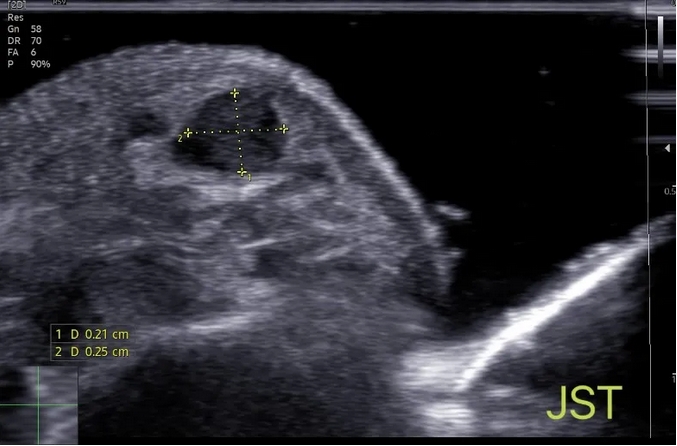

3.3 软组织肿瘤的“侦探”

肌骨超声对于软组织肿瘤的诊断非常有效。它可以协助医生区分良性和恶性肿瘤,评估肿瘤大小、形态和侵犯范围,为手术切除提供精确指导。

软组织肿物在超声图像中各具特点